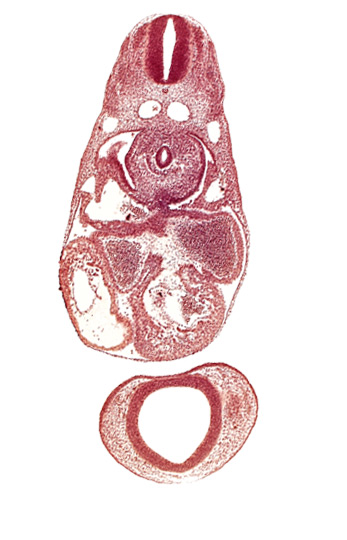

Carnegie Embryo #836 | Location: 07-01-06

Keywords: C-3 spinal ganglion primordium, anterior cerebral plexus, common atrioventricular canal (isthmus), common cardinal vein, dermatomyotome 7 (C-3), dorsal aorta, endocardium, epimyocardium, esophagus primordium, interventricular sulcus, left atrium, notochord, postcardinal vein, prosencephalon (telencephalic part), prosencoel (third ventricle), trabecular part of left ventricle

Source: The Virtual Human Embryo.